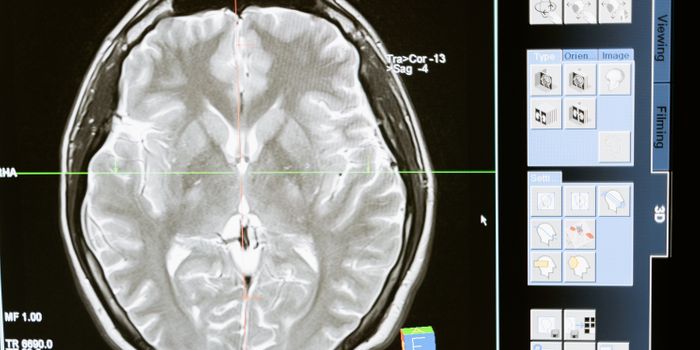

JUN 01, 2023TechnologyA recent study published in Nature explores how artificial intelligence (AI) is being used to better understand the how ...

MAY 18, 2023TechnologyDementia is a debilitating condition. Although not a specific condition per se, it does refer to several conditions that ...

FEB 25, 2023Health & MedicineMRI scans are powerful diagnostic tools. In the 1990s they became commonly used, and contrast agents that contain the ra ...